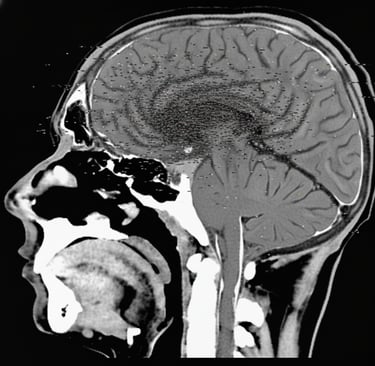

pht. 1965 (Ankara Dr. Sami Ulus Hastanesi'nde çekildi.)

Beynin frontal lobundan parietal lobuna kadar uzanabilen parazit bir tümör beyin kıvrımlarını değiştirip OÇ şeklini almasıyla hastada belli başlı belirtiler ortaya çıkarabilir.